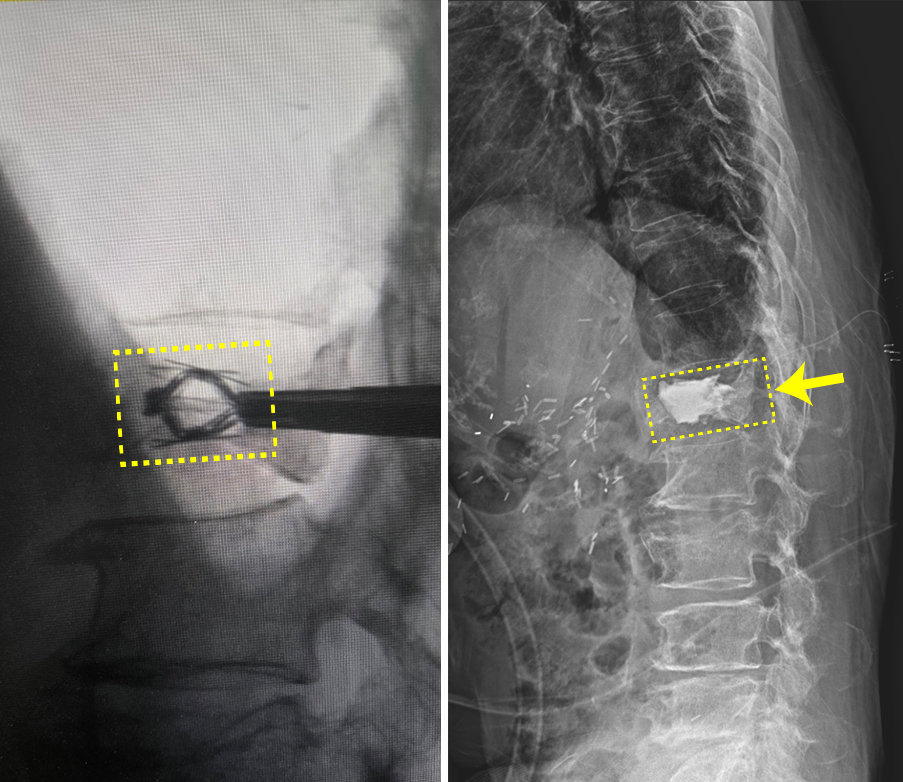

김중호 신경외과 과장은 “임플란트를 이용한 경피적 척추 압박 골절 보강술은 척추체에 상하 축 확장형의 티타늄 임플란트를 삽입해 압박 골절된 척추체를 들어 올린 후 골시멘트를 주입하는 방식”이라며 “임플란트의 삽입 위치와 팽창을 집도의가 제어할 수 있어 무너진 척추체를 보다 정확한 높이로 복원하는데 유리하다”고 말했다.

시술을 집도한 김중호 신경외과 과장은 “척추체의 높이를 올리고 유지해 척추체 복원 및 골절된 뼈를 보강하는 데 효과적으로 활용될 수 있을 것으로 기대한다”고 말했다.